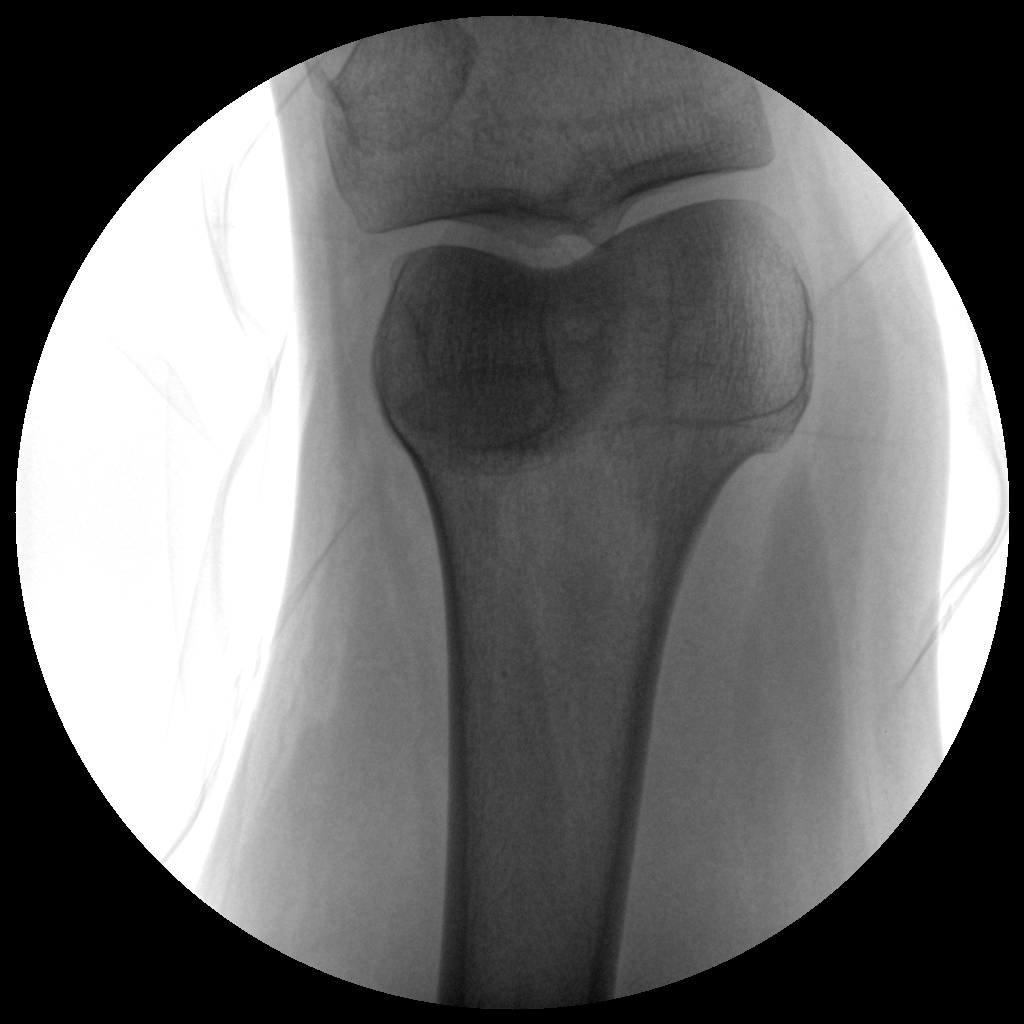

●全數(shù)字化百萬(wàn)像素影像系統(tǒng),圖像清晰

●靈活的C臂機(jī)架設(shè)計(jì),滿足臨床大范圍運(yùn)動(dòng)